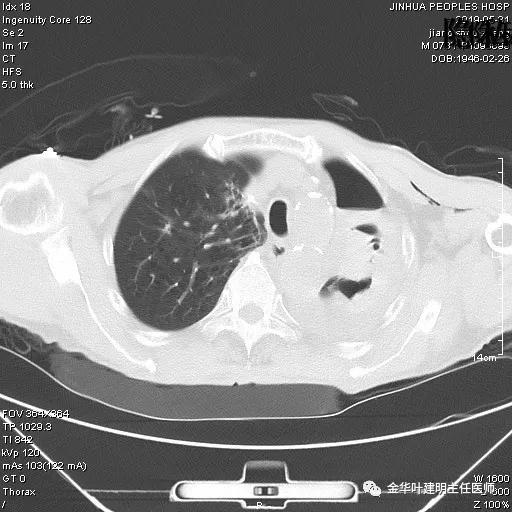

考虑左侧大量胸腔积液,遂进一步胸部CT检查:

以上是肺窗表现,下面为纵隔窗影像:

因为引流出的胸液为血性,但感觉不是特别鲜,查血色素9.5 g/L,术前是12.7g/L。当时考虑胸腔内出血可能,较为纠结的是是否需要进胸探查。但鉴于血压正常、心率不快,一般情况良好,不似胸内大出血休克的表现,所以仍想继续观察保守治疗。